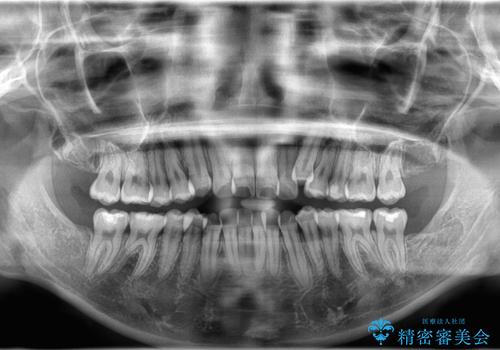

- 八重歯と口元が出ていることを主訴に来院されました。

レントゲンの検査において、前歯も外側に傾いてる結果であったため、上下左右の小臼歯を抜歯して配列を行いました。

歯の動きも良く短期間で治療を終えられたため患者さんにも大変満足していただきました。